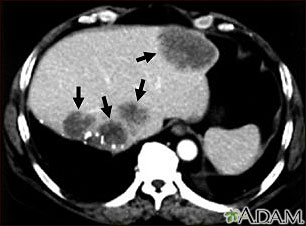

Metastasis is the movement or spreading of cancer cells from one organ or tissue to another. Cancer cells usually spread through the blood or the lymph system.

If a cancer spreads, it is said to have "metastasized."